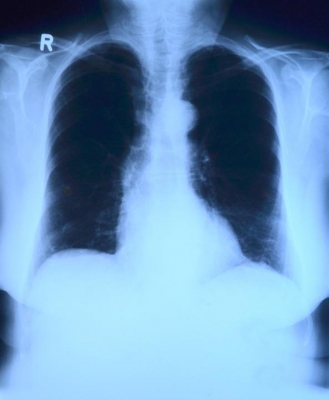

La Mission della struttura è rivolta alla diagnosi e cura delle patologie toraciche che necessitano di un approccio di tipo chirurgico. Le patologie benigne e maligne del polmone costituiscono la parte preponderante della nostra attività, e la stretta adesione ai più aggiornati protocolli internazionali è uno specifico punto di forza.